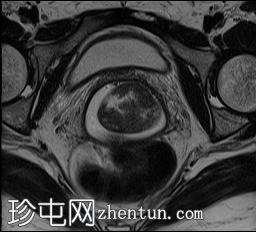

轴位

T1加权像

可见局部晚期浸润性内生型宫颈癌,肿瘤大小为30 x 32 x 48 mm。该肿瘤已侵犯宫颈前唇和后唇的深层间质,以及子宫肌层的下段。

此外,肿瘤还累及宫旁组织。影像学检查发现异常淋巴结肿大,最大短轴直径(SAD)为10 mm,位于髂总血管分叉处和髂内动脉链下方。该淋巴结肿大在弥散加权成像(DWI)上显示水限制,且增强扫描后可见强化。

影像学检查结果提示根据FIGO分期系统,患者为宫颈癌IIIC1期。

宫颈肿块活检的组织病理学报告显示为宫颈鳞状细胞癌。